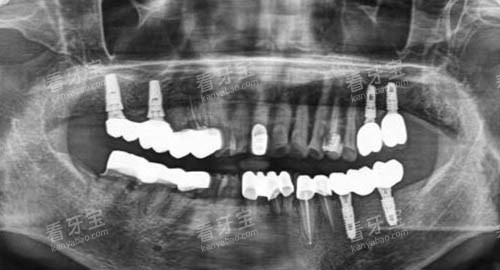

种植牙:适合缺牙或牙齿长期缺失的中年人群,医生会根据口腔骨量制定个性化方案。

种植牙:适合牙齿缺失或老年人群,医生会结合口腔骨量和咬合情况设计方案。

种植牙与牙周手术:适合中老年缺牙或牙龈萎缩人群。

种植牙及复杂修复:适合中老年缺牙或牙齿缺损人群。